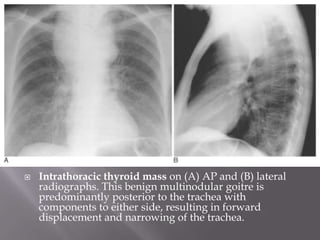

 Intrathoracic thyroid mass on (A) AP and (B) lateral

radiographs. This benign multinodular goitre is

predominantly posterior to the trachea with

components to either side, resulting in forward

displacement and narrowing of the trachea.

 Intrathoracic thyroidmass on (A) AP and (B) lateral radiographs. This benign multinodular goitre is predominantly posterior to the trachea with components to either side, resulting in forward displacement and narrowing of the trachea.